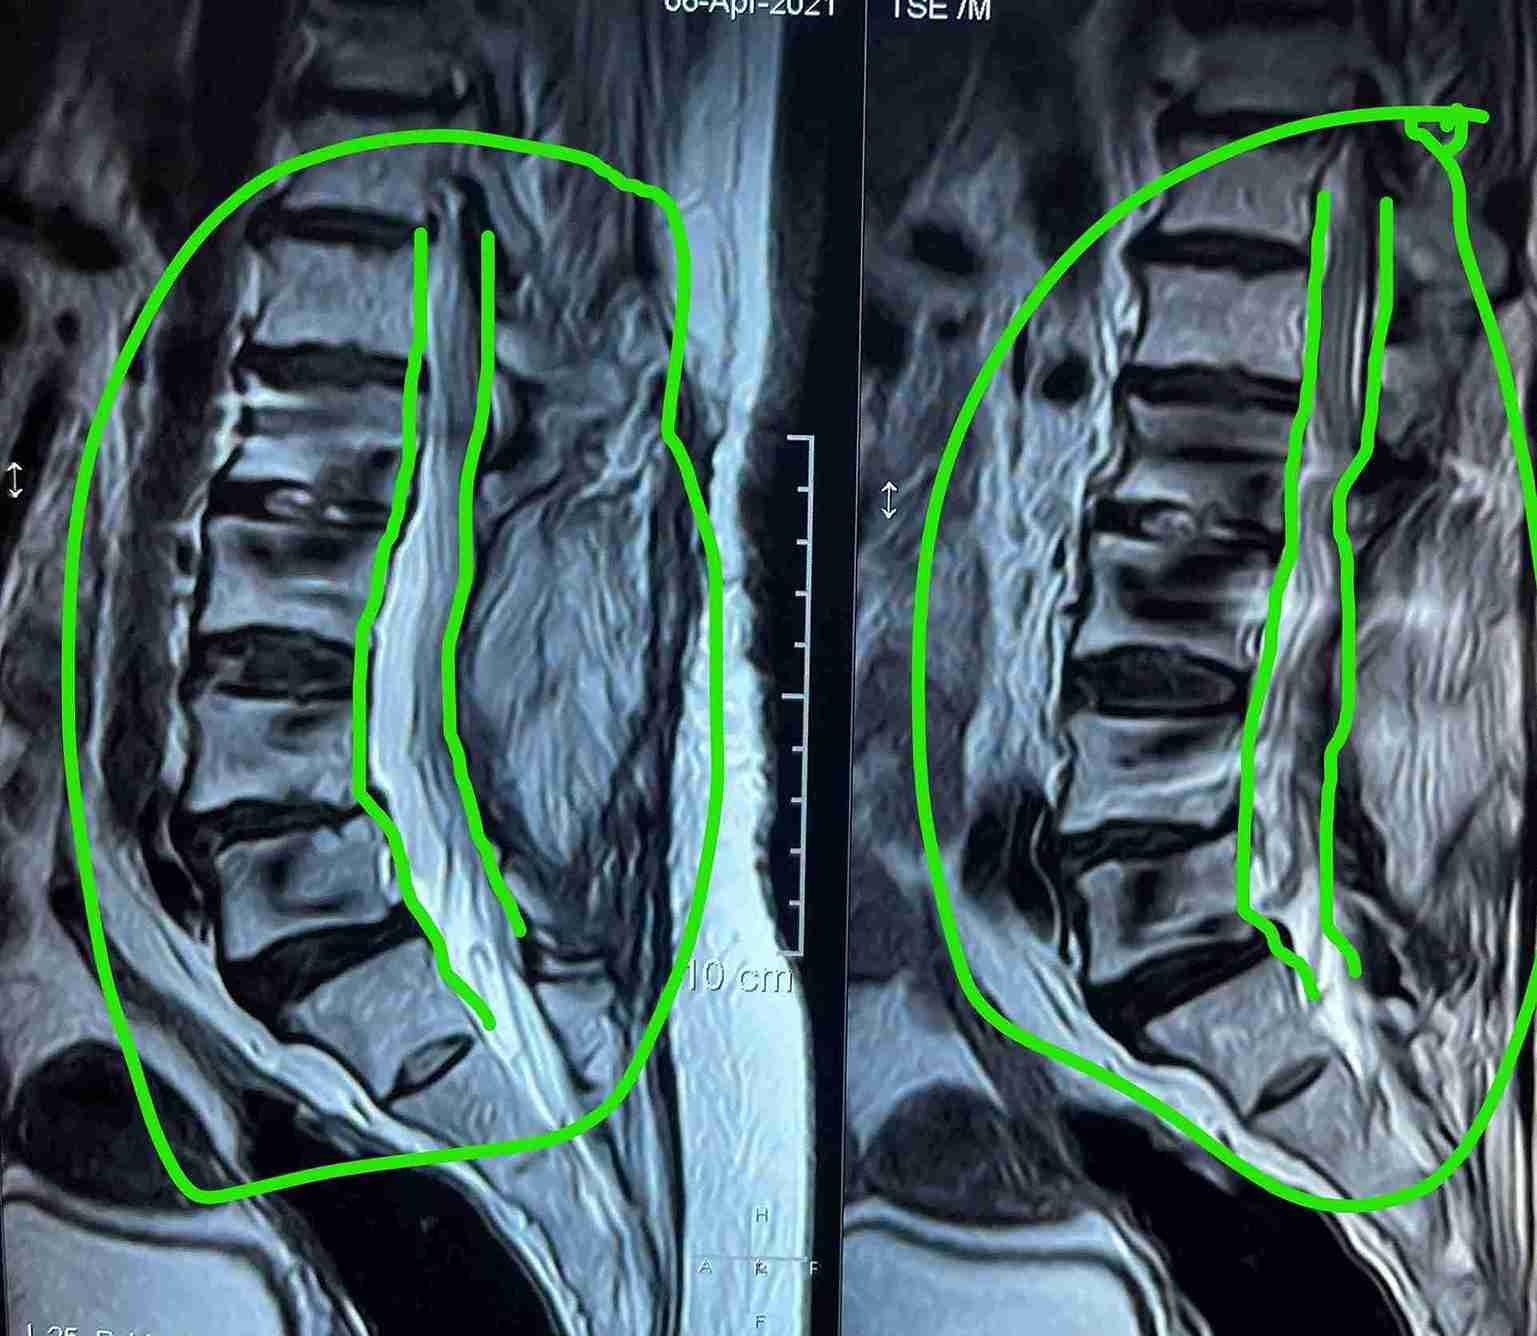

ضيق بالقناة العصبية القطنية مستويات متعددة مع تزحزح فقاري قبل وبعد الجراحة

multiple levels of lumbar nerve canal stenosis with spondylolisthesis before and after surgery

A successful surgery was performed to treat multi-level lumbar spinal stenosis accompanied by spondylolisthesis. This condition causes pressure on the nerves in the spinal column, leading to severe pain and difficulty in movement.

• Severe lower back pain radiating to legs

• Numbness and weakness in lower limbs

• Difficulty walking and standing for long periods

• Gradual deterioration in mobility